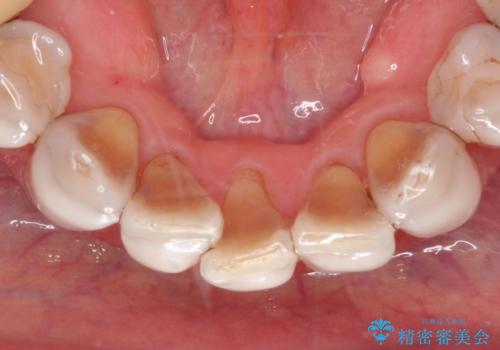

- 昔、他院で治療したダイレクトボンディング(歯の表面にだけ白い材料を盛る治療)のやりかえを主訴に来院されました。叢生の改善も同時に行うためにオールセラミッククラウンにより治療を行いました。

ダイレクトボンディングでの治療より、天然歯に近い見た目を再現することができます。